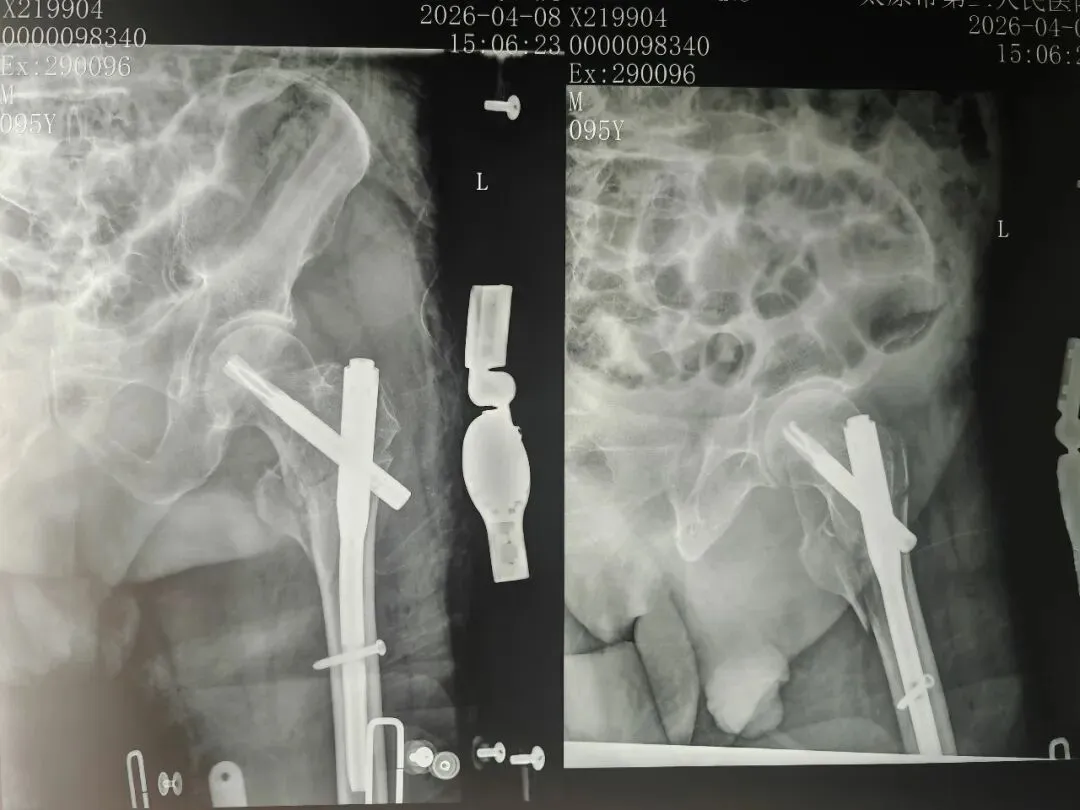

在多学科团队的紧密配合下,医护人员迅速为曾爷爷完善了各项术前检查,并制定了详尽周密的手术方案,麻醉计划及术后康复计划。骨科团队共同为患者施行了左股骨粗隆间粉碎骨折微创内固定术,手术过程顺利,术中出血少,有效缩短了手术时间。

术  后